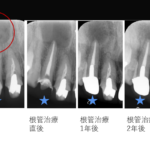

【約10 mmの根尖病変を非外科的根管治療で治癒した症例】「歯茎を押すと膿が出て痛い、他院で半年間治療するも治癒しない。」

「歯茎を押すと膿が出て痛い、他院で半年間治療するも治癒しない。」ということで来院された患者様の症例です。

【約15mmの根尖病変を非外科的根管治療で治癒した症例】「歯茎を押すと痛い、他院で抜歯と言われた。」

「歯茎を押すと痛い、他院で抜歯と言われた。」ということで来院された患者様の症例です。